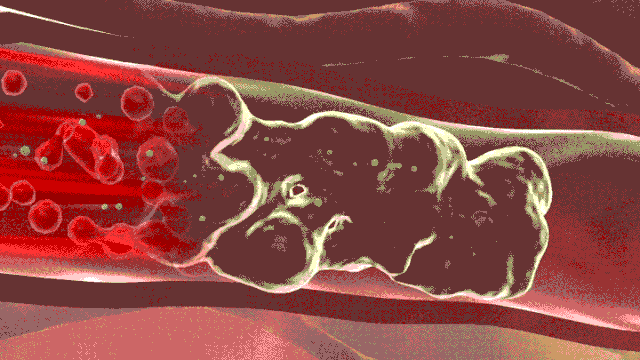

動(dòng)脈瘤并非腫瘤,而是動(dòng)脈壁發(fā)生擴(kuò)張、向外膨出的囊性物體。王主任把腹主動(dòng)脈比作一條自行車(chē)胎,長(zhǎng)期的高壓和老化,導(dǎo)致車(chē)胎變硬,最后形成車(chē)胎的“鼓包”,這個(gè)“鼓包”就是腹主動(dòng)脈瘤。主動(dòng)脈是身體的主干血管,承受直接來(lái)自心臟跳動(dòng)的壓力,血流量巨大,出現(xiàn)腹主動(dòng)脈瘤,如果不進(jìn)行恰當(dāng)和及時(shí)的治療,后果嚴(yán)重。其中最大的風(fēng)險(xiǎn)為瘤體破裂、大出血、死亡,此外,腹主動(dòng)脈瘤形成后,局部血流形成渦流,瘤腔內(nèi)容易形成大量附壁血栓,血栓附于動(dòng)脈瘤腔內(nèi)壁,并不牢固,隨時(shí)可能脫落,造成下肢動(dòng)脈栓塞、肢體嚴(yán)重缺血,治療不及時(shí)可能導(dǎo)致下肢壞死和截肢。